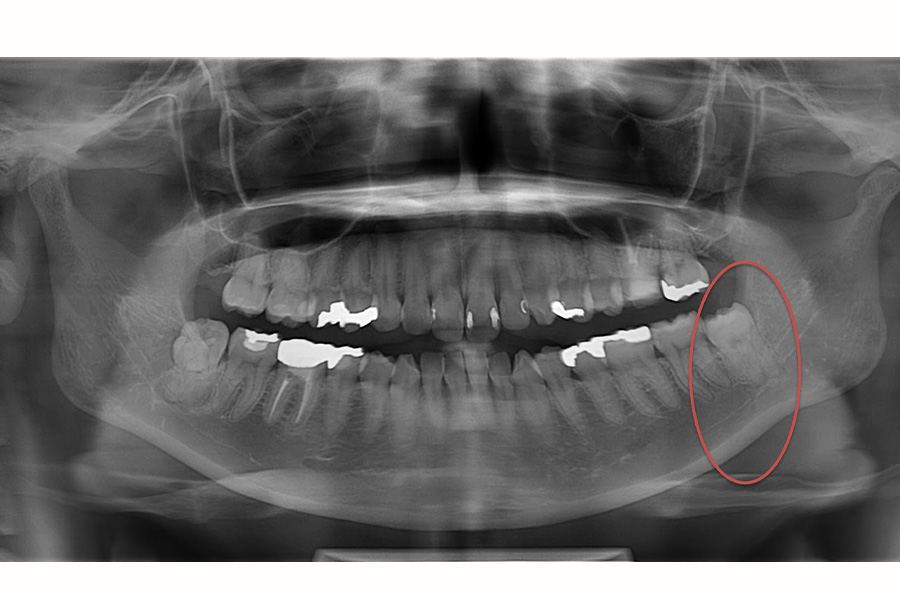

Case.3

治療前

治療後

| 主訴 | 親知らずがの周囲がよく腫れる |

|---|---|

| 治療期間 | 1週間 |

| 治療費 | 保険内治療で約10,000円(CTおよびパノラマレントゲン代を含む) |

| 治療内容 | 右の下の親知らずの周囲の歯肉がよく腫れて、神経と近いので大学病院でないと抜歯できないと他院で断られ当院を受診されました。当日に訪問されて、CT撮影後神経と親知らずの位置関係を確認し、安全に抜歯しました。3週間後また左上下の抜歯を行いました。抜歯した翌日にほとんど腫れはなく、1週間後にも痛みや神経症状もなく、糸取りをして治療終了としました。 |

| 治療のリスク | 下の親知らずは神経の管と近接しているため、一時的に抜歯後唇や舌、歯肉が痺れる症状が出ることがありますが、通常数日後には治ります。 |